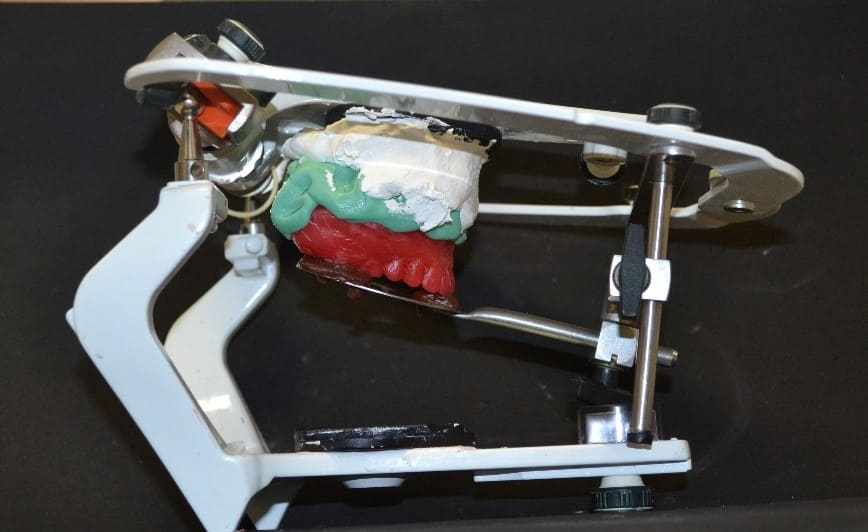

The clone was taken in the mouth to check the adaptation, with no need for adjustments. The assembly was then performed on the semi-adjustable articulator (ASA) (Bio-Art 4000-S, Brazil), for this it was heated to the stick godiva, which was inserted in the fork perforations, subsequent heating was performed and the fork carried in the mouth with the clone for the recording of the molar straps and incisal edges of the anterior teeth. Then, the facial arch was mounted by adjusting the fixation screws (figure 10). After obtaining the records, the base was made with heavy condensation silicone (Zetaplus®, Zhermack, Italy) and the upper orientation plane was mounted on the ASA (figure 11).

Figure 10: Facial arch assembly.

Figure 11: Top model mounted on the ASA.

Then, as the clone was used in the upper arch, there was no need to make adjustments, so the vertical dimension was determined and recorded in the centric relationship position. Then, the orientation plans were fixed with the aid of heated paper clamps (figure 15), and taken to the ASA to fix the lower model. Finally, the set was forwarded to the laboratory to assemble the teeth, with it being completed, and the test was performed, in which it was found that no adjustments in the position of the stock teeth were necessary (figure 16). The next step consisted of the peripheral seal with godiva baton, which was possible to obtain the anatomical details of the desired plateable area and retention (figure 17).